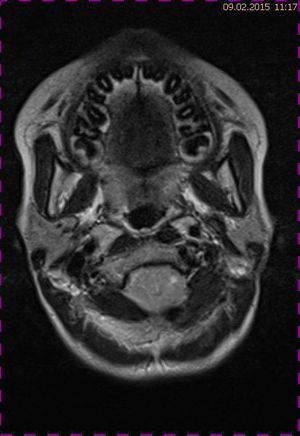

Abb. 2.2 MRT (T2 TSE transversal): obliteriertes Foramen magnum

Das Fallbeispiel 1 zeigt im Verlauf eine Komplikation bei einer Arnold-Chiari-Malformation Typ 1 bei einem zum Zeitpunkt der Erstdiagnose 12-jährigen Jungen. Dieser hatte im Sportunterricht einen schweren Medizinball geköpft und ein Stauchungs-trauma der Halswirbelsäule erlitten. Nach anfänglich symptomatischer frustraner Therapie wurde er vom behandelnden Orthopäden zur MRT der HWS überwiesen. Es wurde eine Streckfehlhaltung und flachbogig rechtskonvexe Skoliose diagnostiziert, klinisch bestand ein Torticollis. Eine knöcherne oder ligamentäre Verletzung wie auch eine Schädigung des Rückenmarks bzw. eine intraspinale Bandscheibendislokation konnten bildmorphologisch ausgeschlossen werden.

Trotz weiterer Schmerz- und Physiotherapie konnte keine Beschwerdereduktion erreicht werden. 2 Monate später erfolgte eine MRT des Kopfes zum Ausschluss einer posttraumatischen Veränderung.

Bei dieser Untersuchung wurde übersehen, dass die Kleinhirntonsillen in das Foramen magnum disloziert waren und eine Arnold-Chiari-Malformation mit Erweiterung des 4. Ventrikels und des Aquäduktes inklusive Kleinhirntonsillentiefstand vorlag. Bei zwischenzeitlich auswärtig erfolgtem CT der HWS wurde eine Anlagestörung im kraniozervikalen Übergang beschrieben. Eine Kontrolluntersuchung des Kopfes weitere 4 Monate später dokumentierte neben einem medullären Ödem einen progredienten Tonsillentiefstand, der zur neurochirurgischen Behandlung mit operativer Erweiterung des Foramen magnum führte.